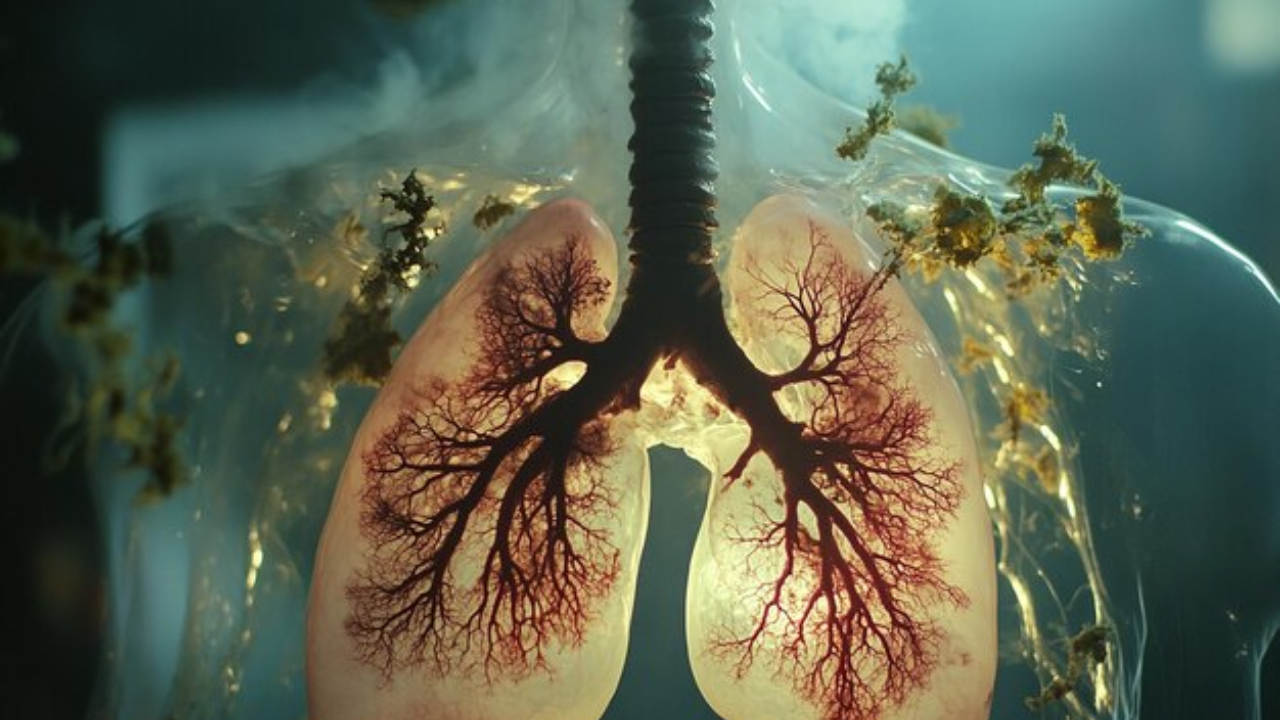

World Lung Day 2024 Lung Problem Signs In Hindi: हम लगातार सांस लेते व छोड़ते हैं। ऐसा करना बहुत जरूरी होता है। क्योंकि जब हम सांस लेते हैं, तो इस तरह हमारे शरीर में ऑक्सीजन पहुंचती हैं, वहीं जब हम जब सांस छोड़ते हैं तो शरीर में मौजूद कार्बन डाइऑक्साइड बाहर निकलती है। शरीर में साफ हवा का पहुंचना बहुत आवश्यक है। ऑक्सीजन के बिना व्यक्ति जीवित नहीं रह सकता है। शरीर के भीतर ऑक्सीजन को पहुंचाने और गंदी हवा को बाहर निकालने में हमारे फेफड़े बुहत अहम भूमिका निभाते हैं। इसलिए अन्य अंगों की तरह फेफड़ों को सबसे महत्वपूर्ण अंगों में से एक माना जाता है। अगर हमारे फेफड़े ठीक से काम नहीं करते हैं, तो इसकी वजह से शरीर में कई स्वास्थ्य समस्याएं पैदा हो सकती हैं।

लेकिन आजकल हम देखते हैं कि लोगों में सांस और फेफड़ों से संबंधी समस्याएं लगातार बढ़ रही हैं। इनमें फेफड़ों में इन्फेक्शन, अस्थमा, पल्मोनरी फाइब्रोसिस, एस्बेस्टॉसिस जैसी गंभीर स्थितियां शामिल हैं। इन स्थितियों में व्यक्ति को सांस लेने में काफी परेशानी होती है। व्यक्ति अस्थमा अटैक जैसी स्थितियों का सामना भी करना पड़ सकता है। ऐसे में यह बहूत जरूरी है कि आप अपने फेफड़ों के स्वास्थ्य का खास ध्यान रखें। लोगों को फेफड़ों के महत्व को समझाने और उन्हें इससे जुड़ी बीमारियों की रोकथाम को लेकर जागरूक करने के लिए हर साल 25 सितंबर को विश्व लंग दिवस मनाया जाता है।

फेफड़ों से जुड़ी बीमारी होने पर दिखते हैं कई लक्षण - Lung Problems Symptoms In Hindi

जब हमारे फेफड़ों में किसी तरह की समस्या होती है और वे ठीक से फंक्शन नहीं करते हैं, तो हमारे शरीर में इसके कई संकेत और लक्षण देखने को मिलते हैं। अच्छी बात यह है कि अगर इन लक्षणों को समय रहते पहचानकर डॉक्टर से सही उपचार लिया जाता है, तो किसी भी तरह के गंभीर नुकसान से बचा जा सकता है। फेफड़ों से जुड़ी समस्या होने पर आमतौर पर ये लक्षण दिखते हैं,